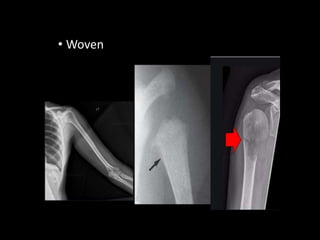

• Woven

Lamellar